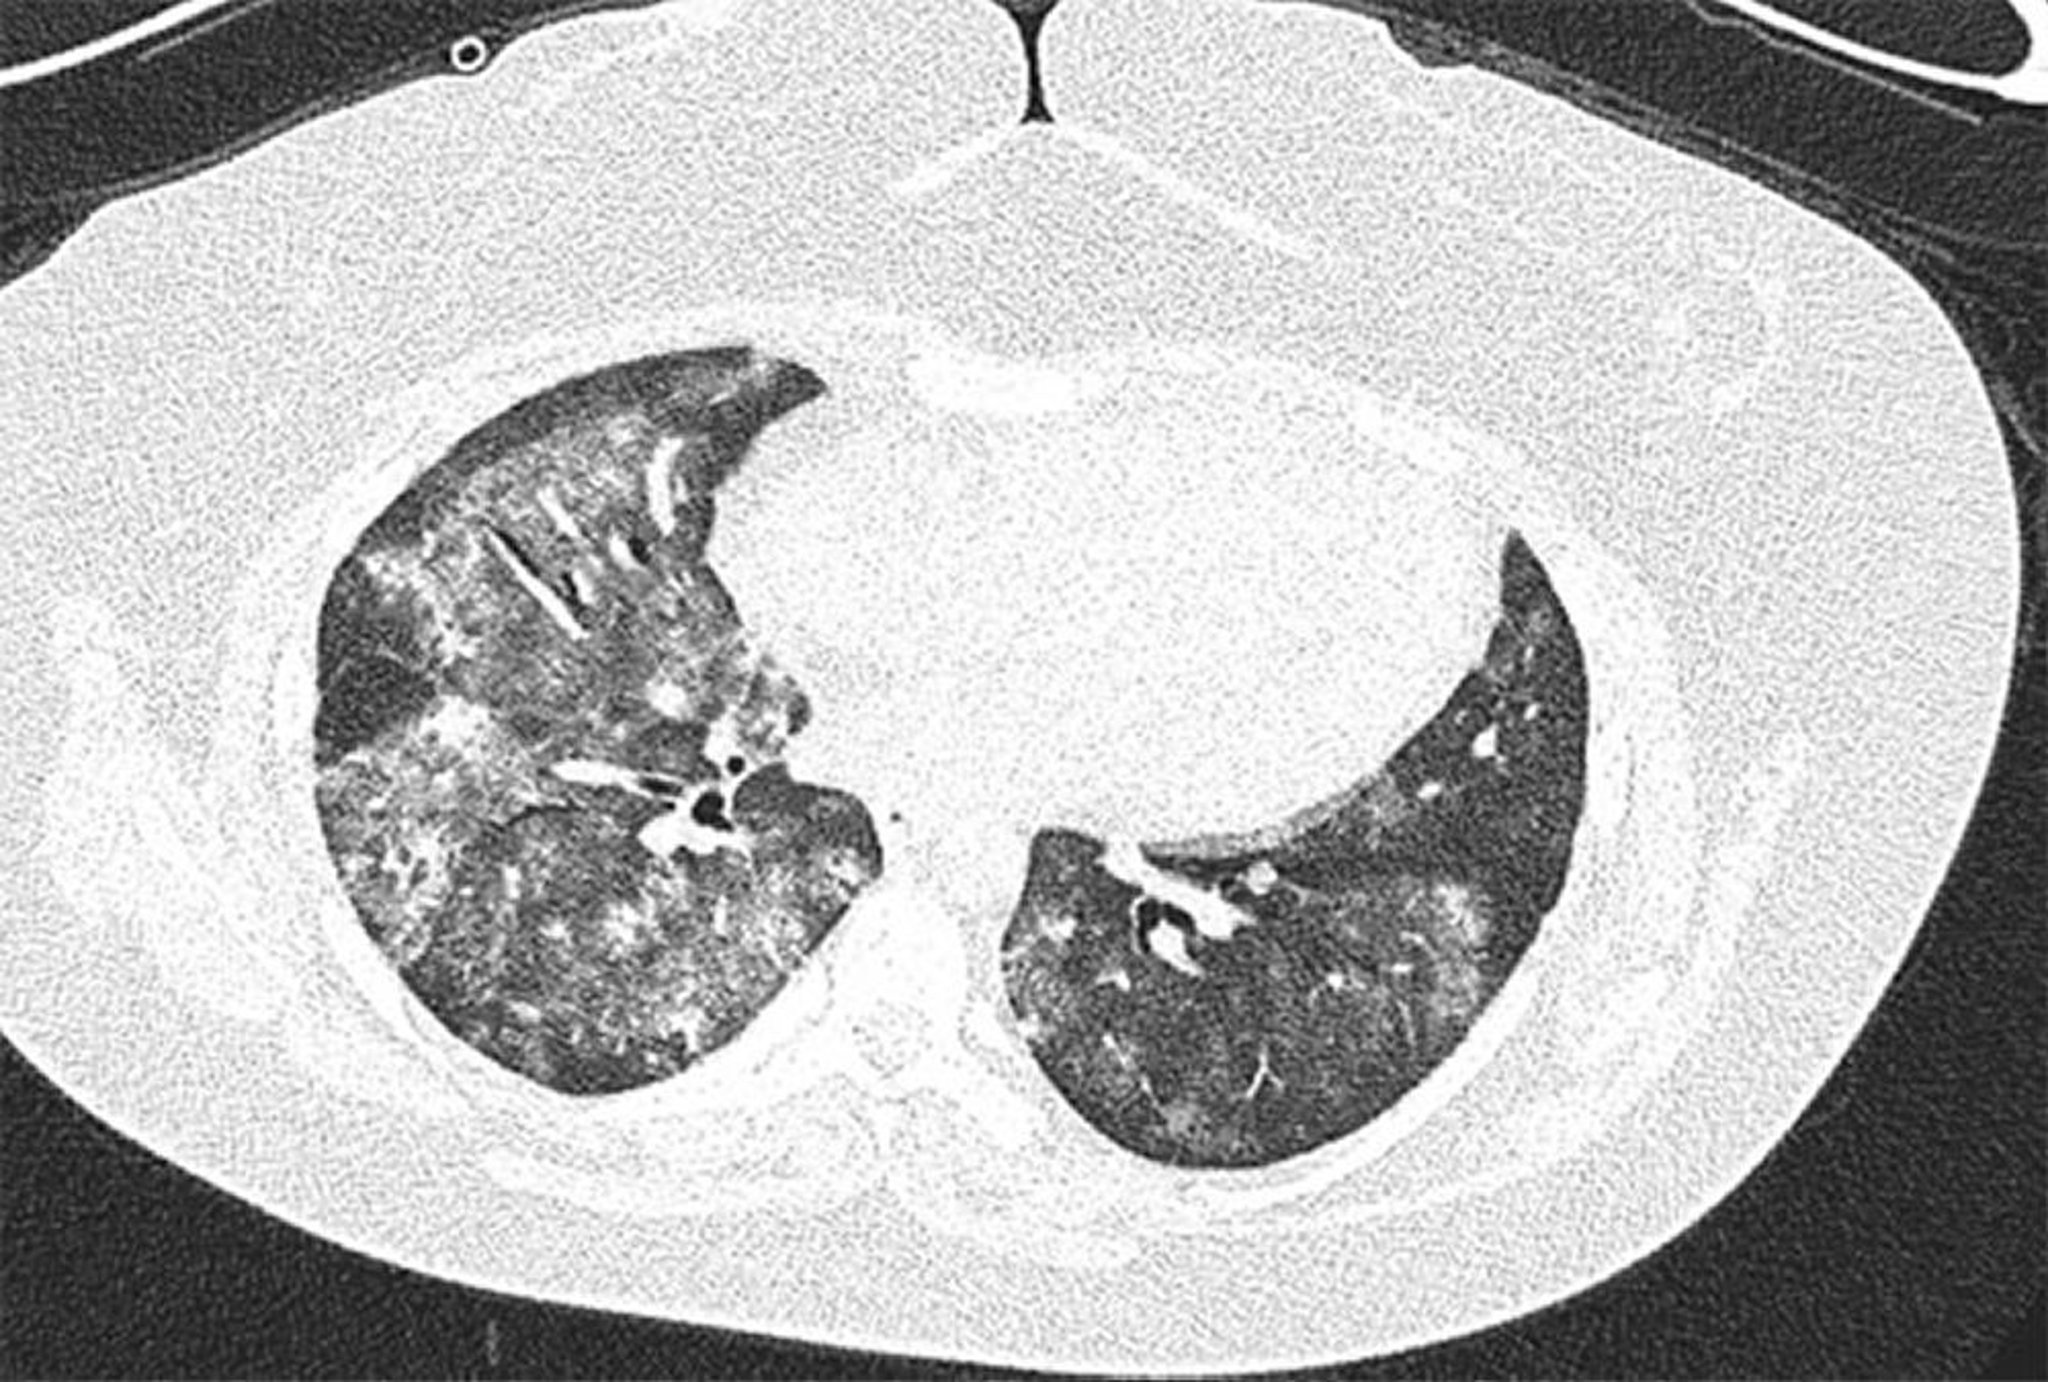

High- resolution CT image of 28-year-old female with antiphospholipid syndrome with recurrent diffuse alveolar hemorrhage. Image shows bilateral and patchy alveolar ground glass opacities with subpleural sparing. Bronchoalveolar lavage confirmed alveolar hemorrhage.

Image courtesy of Joyce Lee, MD.